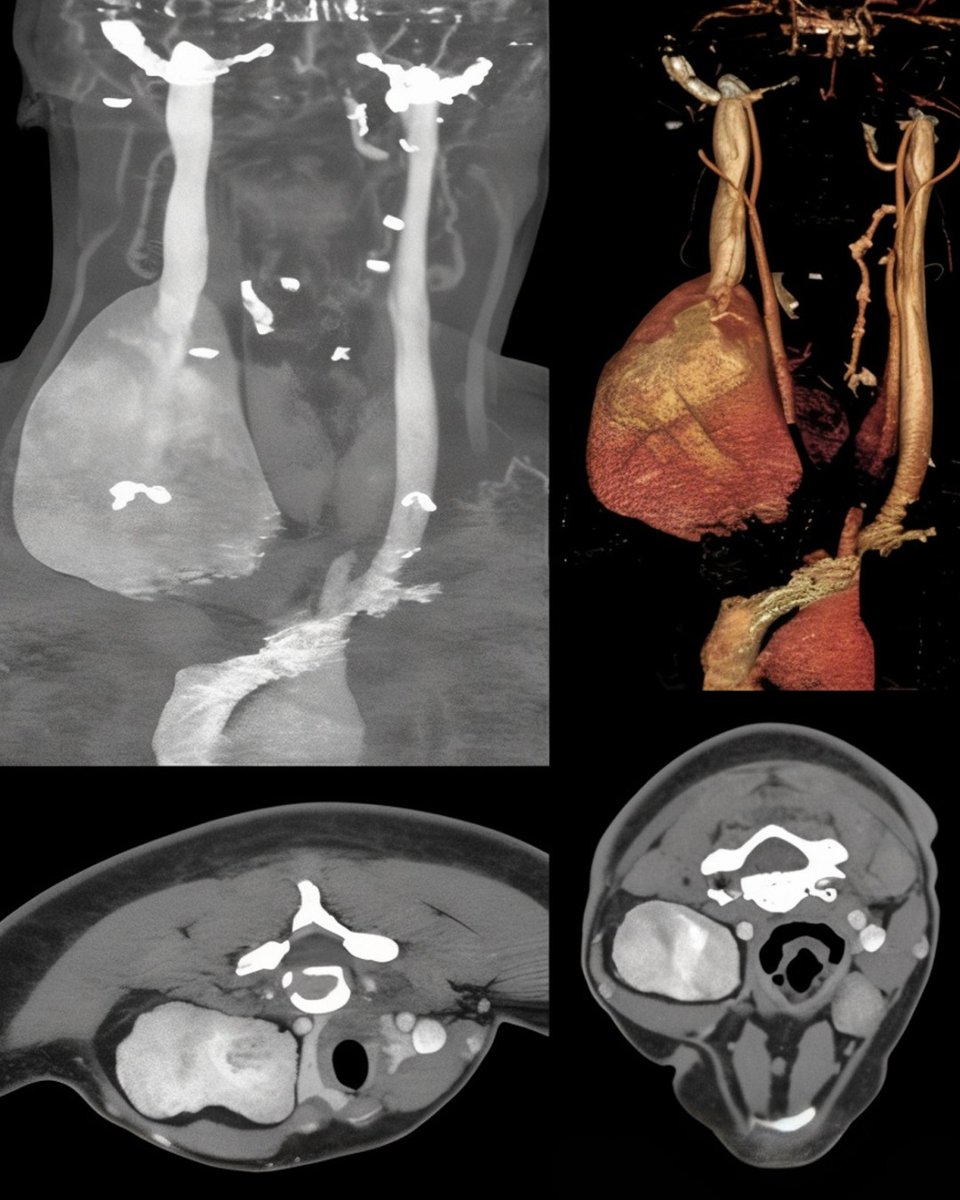

When the IMA is larger than the occluded aorta a EJVES « coup d’oeil » from CHU de Bordeaux OR by our 🇮🇹resident Marco Campolmi An Inferior Mesenteric Artery Too Good To Go sciencedirect.com/science/articl… #aortaEd

When the IMA is larger than the occluded aorta

a <a href="/EJVES_ESVS/">EJVES</a> « coup d’oeil » from <a href="/CHUBordeaux/">CHU de Bordeaux</a>  OR  by  our 🇮🇹resident Marco Campolmi An Inferior Mesenteric Artery Too Good To Go sciencedirect.com/science/articl… #aortaEd